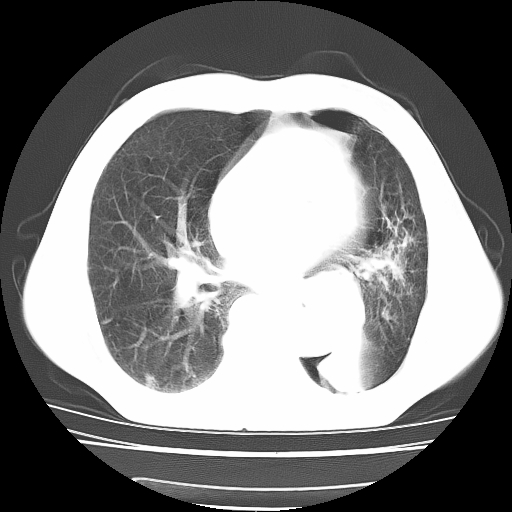

男,71岁,咳嗽,气喘10年,再发并咯血.胸片见气胸

考虑  左肺中心型肺癌伴阻塞性肺炎,肺不张,纵膈淋巴结肿大。慢支炎,肺气肿,左侧气胸肺压缩5%

左侧中央型肺癌伴纵膈淋巴结转移。

左肺中心型肺癌伴阻塞性肺炎,肺不张,纵膈淋巴结肿大

1)考虑左肺中心型肺癌伴阻塞性肺炎、左肺下叶肺不张、左侧肺气肿,纵膈淋巴结转移。2)左侧气胸(肺组织压缩约5%)。

左肺中心型肺癌伴阻塞性肺不张、肺气肿 。

1)考虑左肺中心型肺癌伴阻塞性肺炎、左肺下叶肺不张、左侧肺气肿,纵膈淋巴结转移。2)左侧气胸。